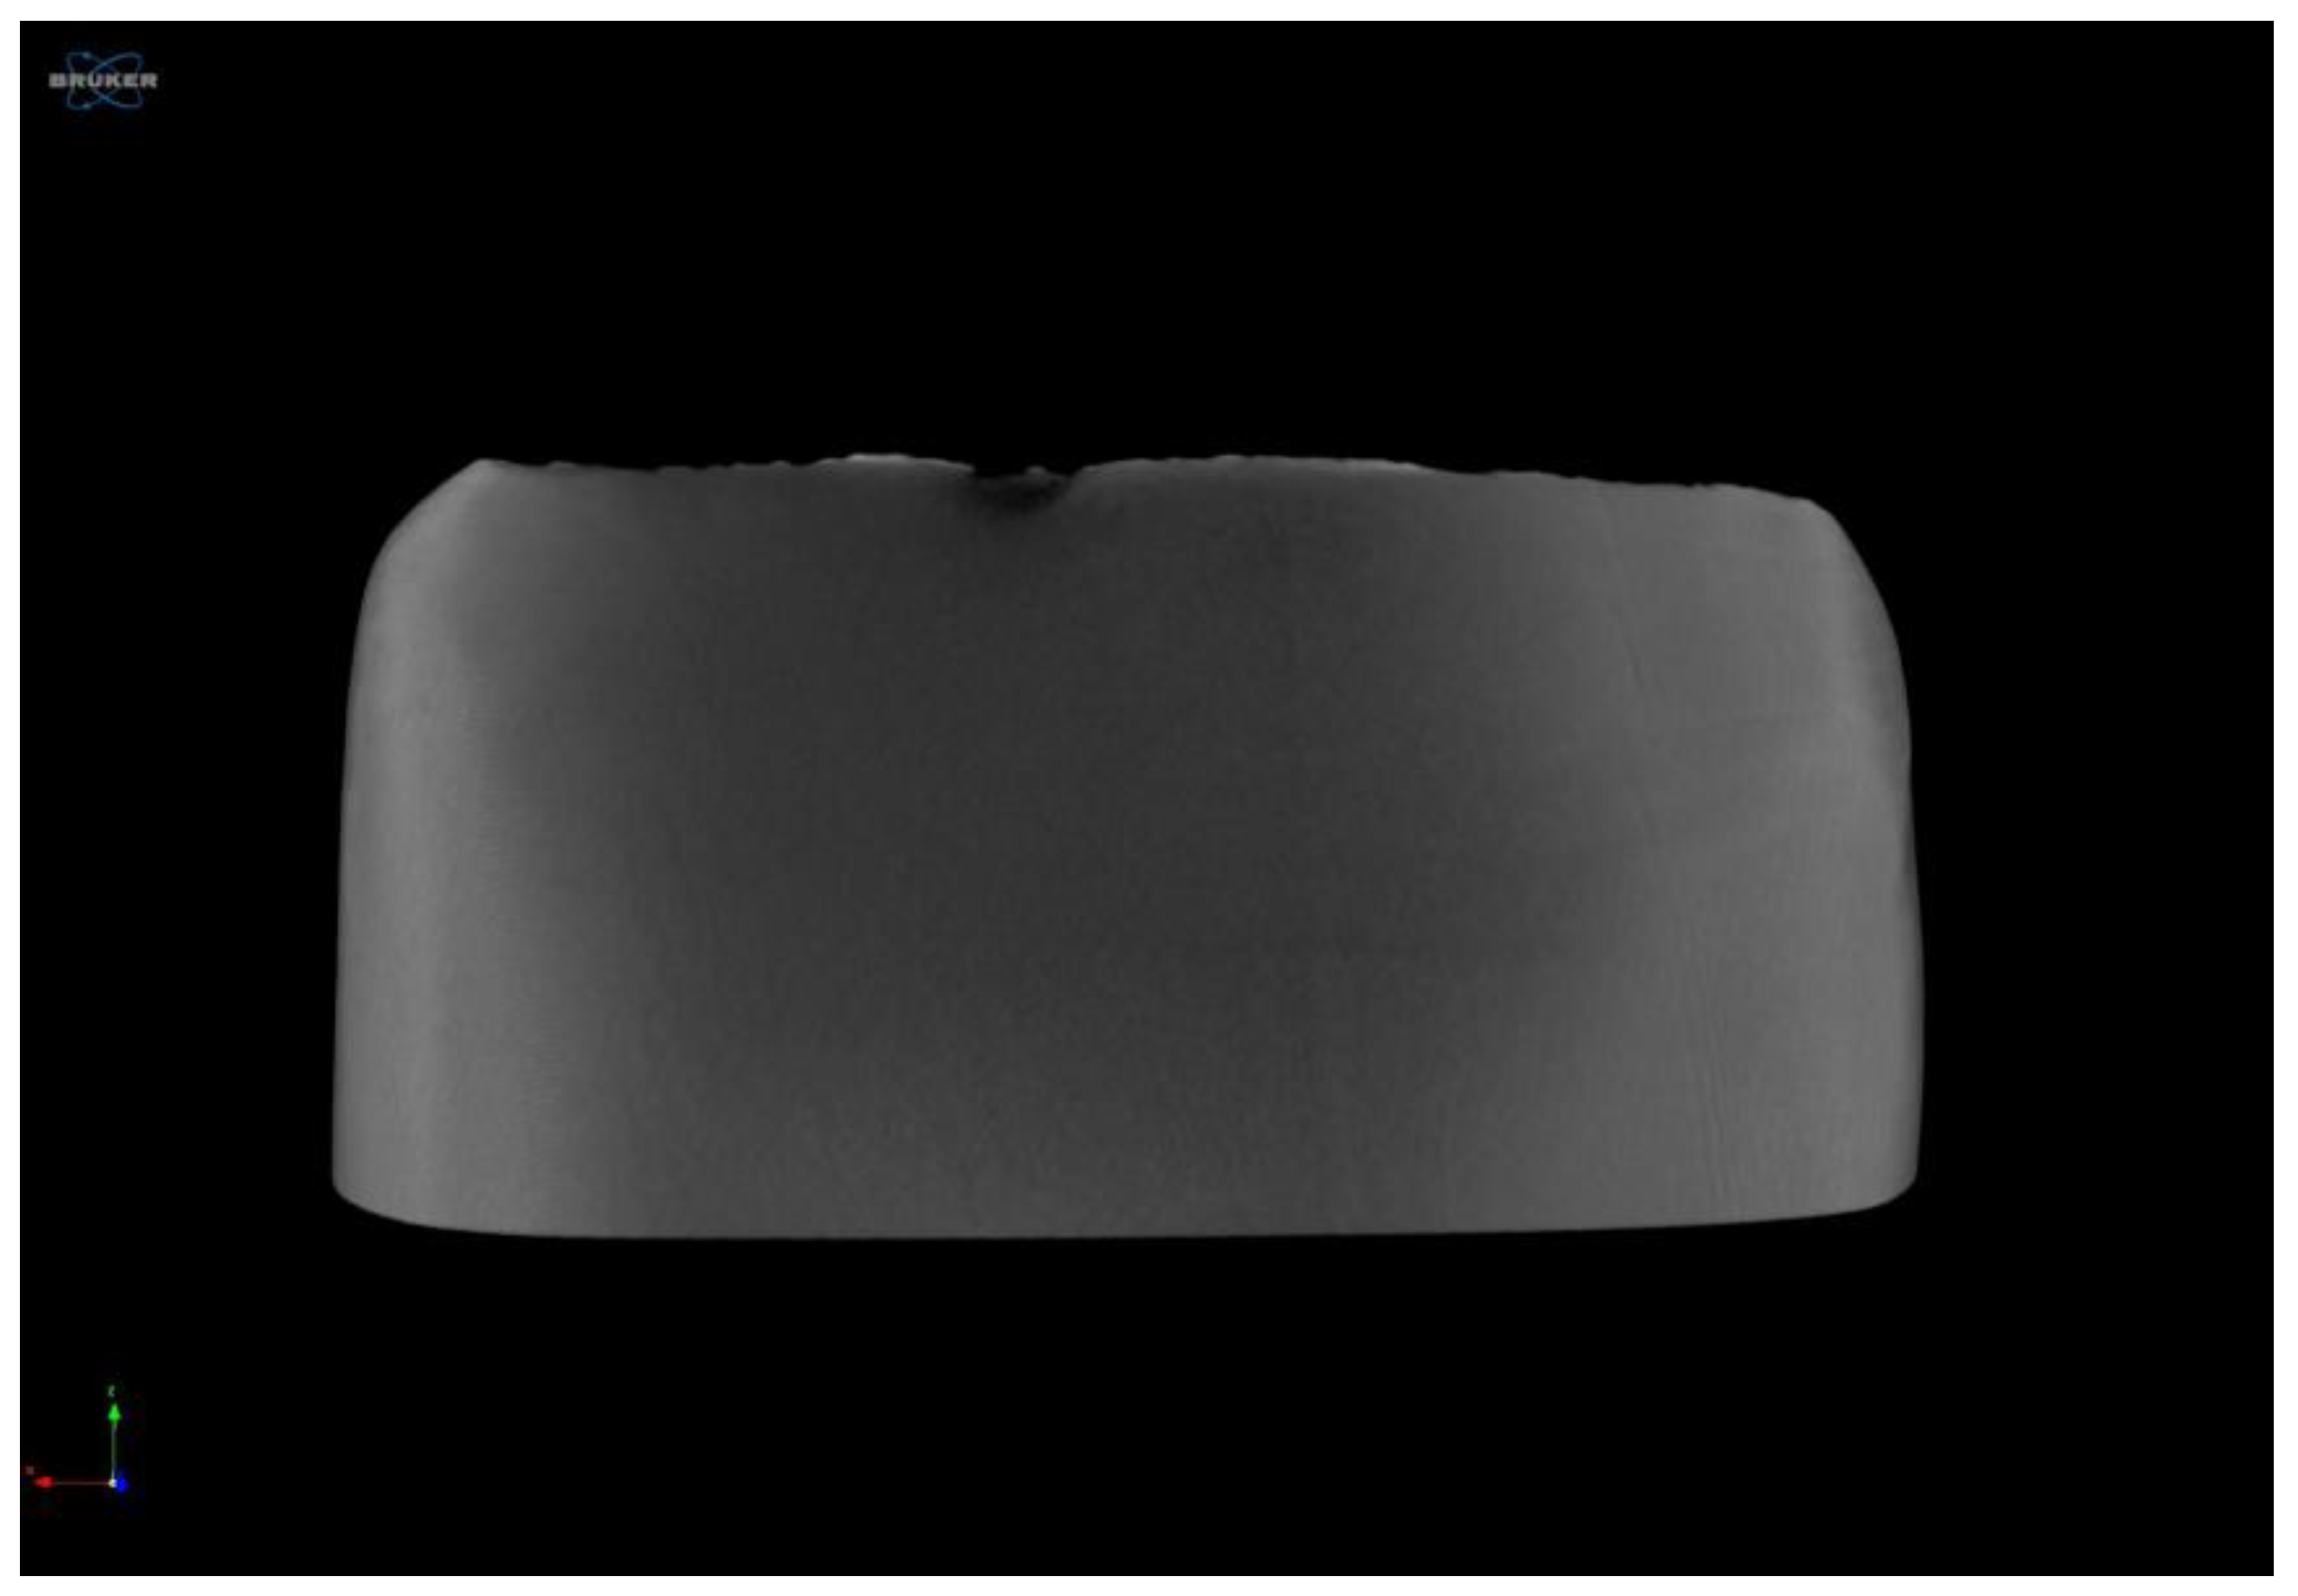

Flaw Generation in a Specimen